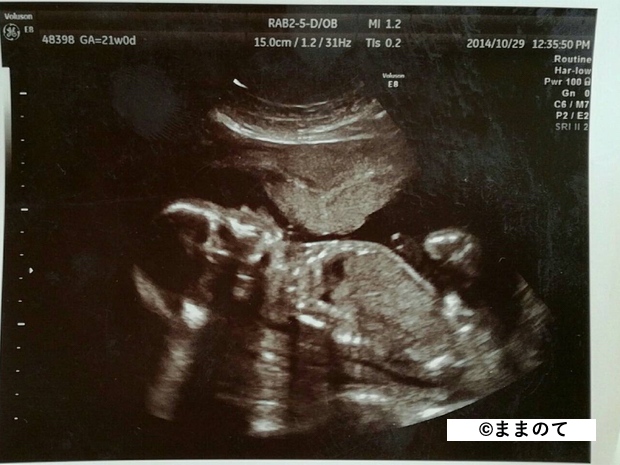

妊娠6ヶ月(20・21・22・23週)

赤ちゃんの骨格や顔立ちがしっかりしてきます。羊水を飲んで呼吸の練習を開始します。心臓が完成してくるため、エコー写真には心臓の弁の動きがはっきりと写し出されます。

身長は約30cm、体重は600~650gほどです。まだ脂肪は多くありませんが、3Dエコーや4Dエコーで全身が見られる時期のため、記念に受診する人もいるようです。

上のエコー写真では、股間からおちんちんが出ているのが見え、男の子だということがわかります。